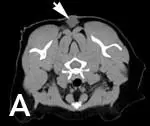

Tumor volume on CT scans with contrast has been shown to be approximately double that of tumor volume measured with calipers on examination4 (Figure 2). This underscores the aggressive nature of ISS as well as the importance of advanced imaging for treatment planning.

Figure 2 (View larger image). CT scan of a cat with recurrent intrascapular injection site-sarcoma. (A) Intrascapular mass (arrow) palpable on examination and (B) extension of mass caudally and laterally (arrows).